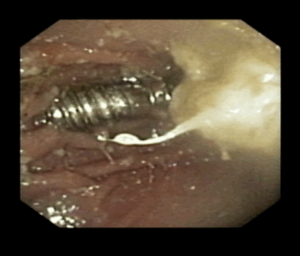

Kat die een schroef heeft ingeslikt -deze bevindt zich op de röntgenfoto in de maag, omdat het risico te groot werd ingeschat dat het vast zou kunnen lopen in een darm is tijdens een endoscopie de schroef verwijderd.

Schroef in de maag van een kat. Deze is succesvol verwijderd door middel van een endoscopie op het MCD.